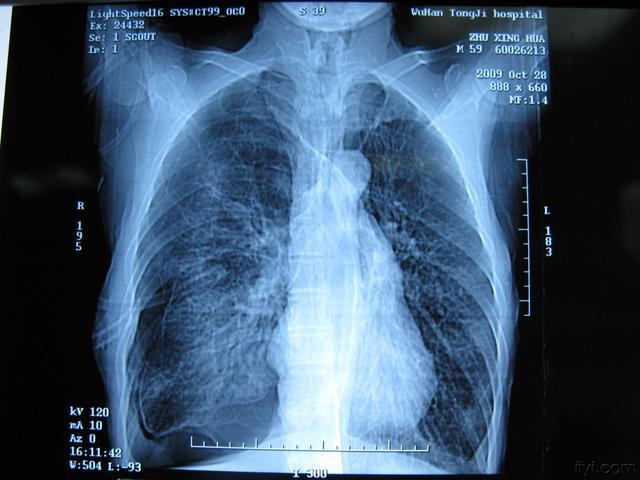

在这个充满生机的世界里,有一种无声的疾病,它悄然侵袭着人们的肺部,它就是肺蛋白沉积症。它不像感冒那样来得轰轰烈烈,却以一种几乎无法察觉的方式,慢慢地剥夺着患者的呼吸自由。

肺蛋白沉积症,这个名词听起来或许有些陌生,但它带来的影响却是实实在在、触手可及的。它让原本可以自由翱翔在蓝天之下的灵魂,被迫在狭小的空间里挣扎求生。